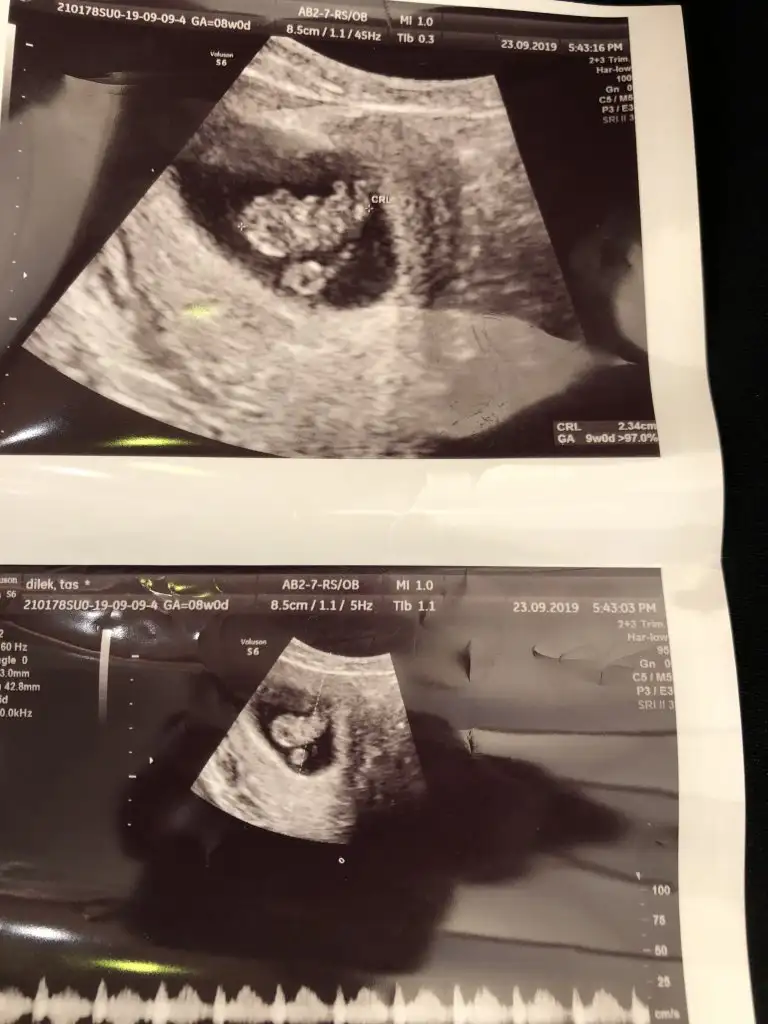

Eki Görüntüle 2538868 Merhaba 8+0 bizedir bir tahmin yapabilir misiniz?